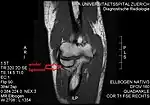

Annular ligament of radius

Annular ligament

Capsule of elbow-joint (distended). Anterior aspect.

Annular ligament of radius, from above. The head of the radius has been sawn off and the bone dislodged from the ligament.